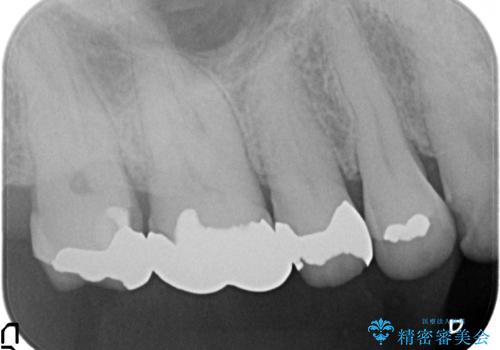

右上6,7の金歯を外したところ、虫歯が歯茎より深い位置まで進行していたため歯周外科を行いました。

虫歯が進み歯茎より深くなってしまうと、虫歯を取り残してしまうリスク、樹脂の硬化の妨げ、補綴物の不適合、歯肉炎・歯周病のリスクの増大等様々な弊害が起こり得ます。

そのため当院では歯周外科手術(歯茎を下げる手術)や歯の挺出による、虫歯が歯茎より深いという問題の解決を推奨しております。